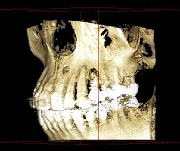

ですから、インプラントや歯周病などの診断に有効で、従来の平面画像では難しいとされた骨の幅の確認などが行えます。CT撮影で様々な角度から診断することで、正確な診査・診断に役立ち、より安全で確かな治療を行うことが可能となりました。

CT画像からは、骨の形や欠損状態がわかるだけでなく、神経の位置や向きなどもしっかり把握できますので、特に、以下のような治療で役立っています。